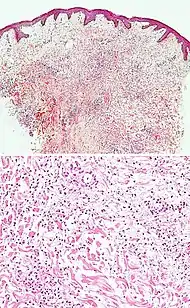

| Cutaneous small-vessel vasculitis |

|

![]() |